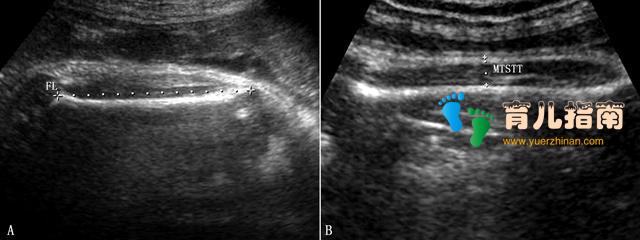

3.皮下软组织厚度 胎儿软组织是影响胎儿体重的重要因素。脂肪组织厚度是反映胎儿出生体重的一个良好的独立性指标。

(1)大腿中部皮下组织厚度 测量股中部股骨表面至皮肤表面的距离(图2)其与胎儿体重具有良好的相关性((r 2 =0.656, p<0.001)。当MTSTT为15mm时,对正常范围的出生体重预测的敏感性和特异性可达87%和89%;20mm时诊断巨大儿的敏感性为91%、特异性为94%。

图2大腿中部皮下组织厚度测量